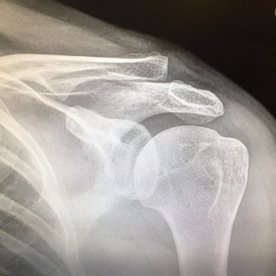

Nigel then promptly offered catching practice to the gully (must be a union relations thing), and we are about 60-5. Some sound words of advice from Growler Major to the incoming Growler Minor obviously didn't work as he went back first ball caught and bowled. 60 odd for 6. Some semblance of calm arrived with Monty Lynch, as we applied ourselves to stop the collapse. However, the hamstrung Growler then asked Nick to make a quick single. In Monty's effort to avoid being run out, he also had to jump over the fast approaching ball, diving like Tom Daly, only forgetting there was no water where he was due to land. The resulting impact is in the match photo as Nick had to wend his way to Frimley Park Hospital to have his shoulder looked at. I personally thought he would have been better batting on with one arm (his right arm was OK after all) and going to A&E at tea, but with the clavicle pointing upwards in a nice lump he had to reluctantly withdraw.